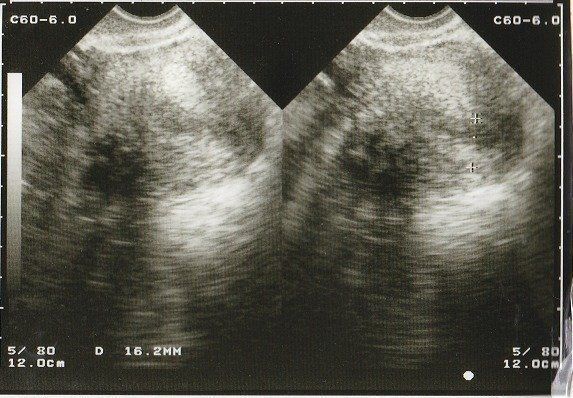

妊娠18週目のエコー写真 画像におさまらないほどに成長する

赤ちゃんがどんどん大きくなり、1枚の超音波画像ではおさまりきらなくなりました。画像を2枚くっつけて赤ちゃんの大きさを測っています。

BPD(児頭大横径=頭の直径)を測って、胎児の発育を調べるようです。ここまで、母子ともに特に異常も無く過ごせました。